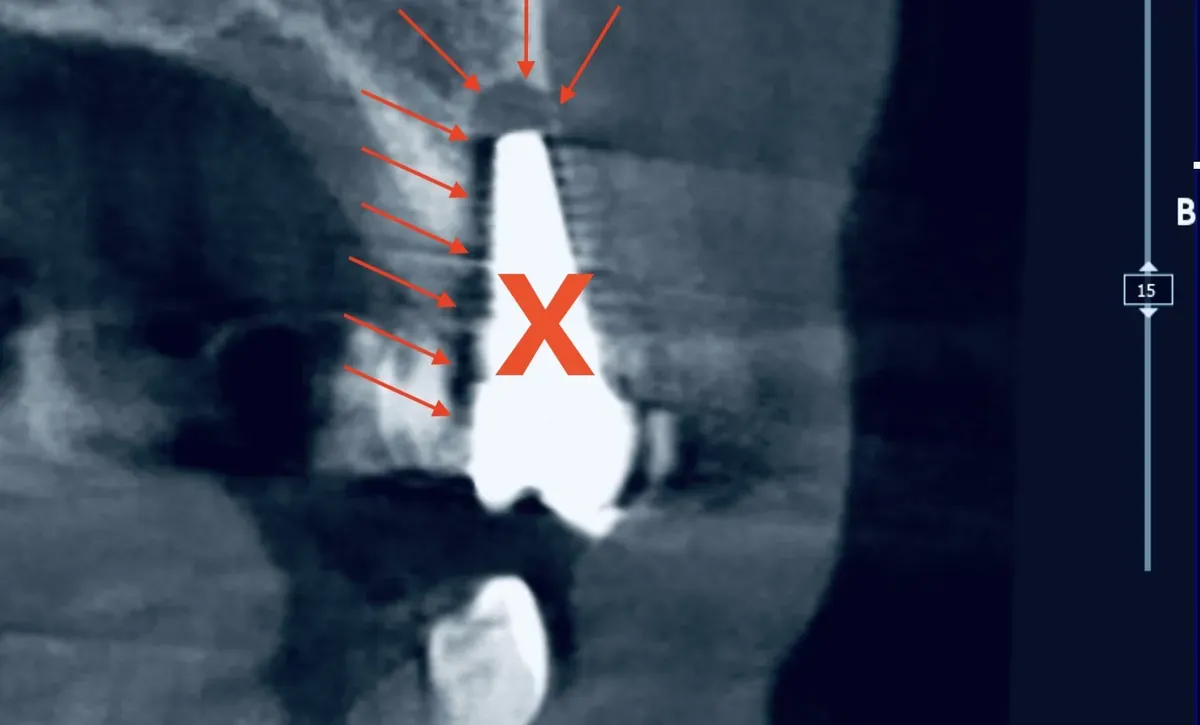

CBCT di un impianto dentale fallito con perdita ossea peri-implantare

Il fallimento tardivo è un’altra storia. L’impianto ha funzionato per anni, poi comincia a perdere osso. La causa più frequente è la peri-implantite — un’infiammazione cronica dei tessuti intorno all’impianto, molto simile alla parodontite che colpisce i denti naturali.